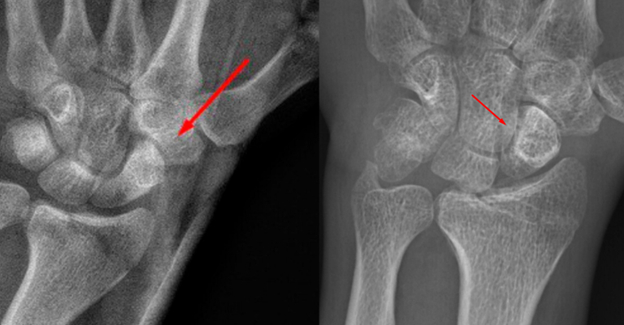

Слева сразу после перелома. Справа как сейчас.